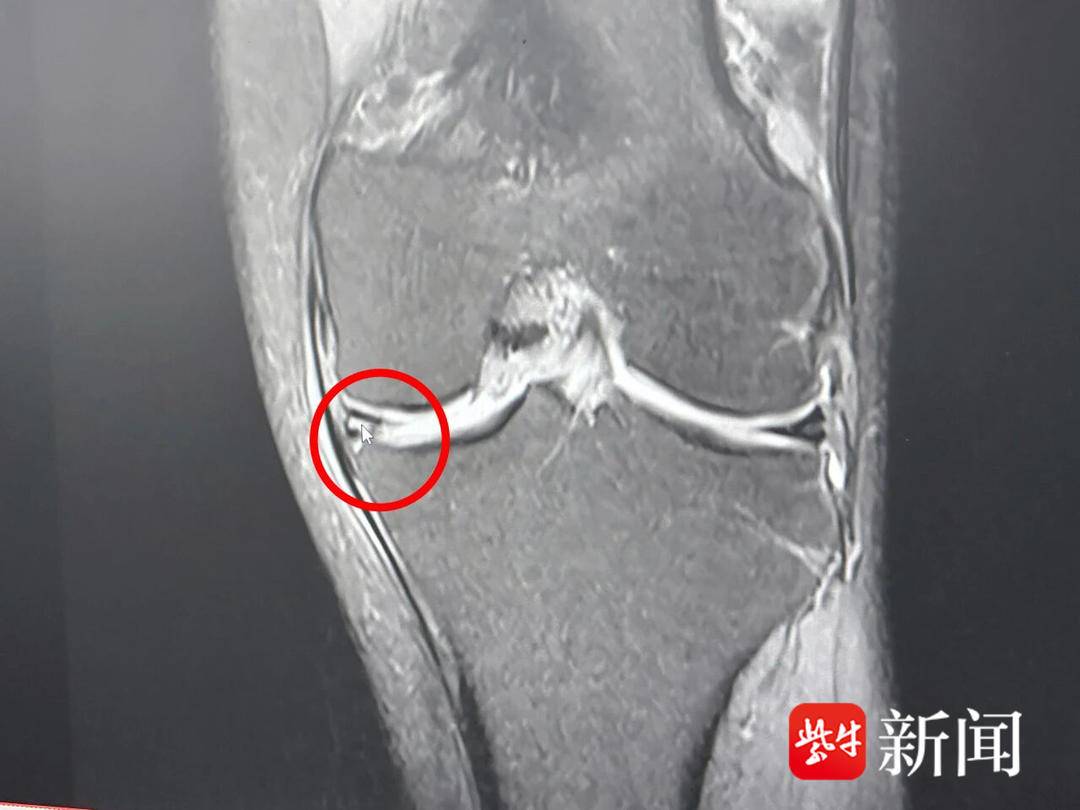

患者损伤的半月板。通讯员供图

在膝关节骨性关节炎患者中,最常见的就是半月板损伤。“关节软骨逐渐退化、变薄和磨损是主要原因,你看这位患者的左侧半月板后方已经‘稀烂’,走路时骨头之间相互摩擦,疼痛在所难免。”江都人民医院关节外科主任袁永建指着电脑屏幕上高师傅的片子解释道。“像他这种情况,保守治疗已经不能解决问题,再加上他才50多岁,保膝治疗更为必要!”